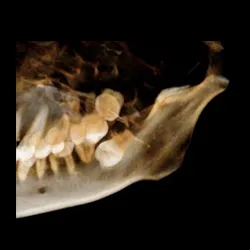

• 3D image system

• Precise location of impacted teeth

• Precise measurement of implant placement

• Bone loss visualization

Case3